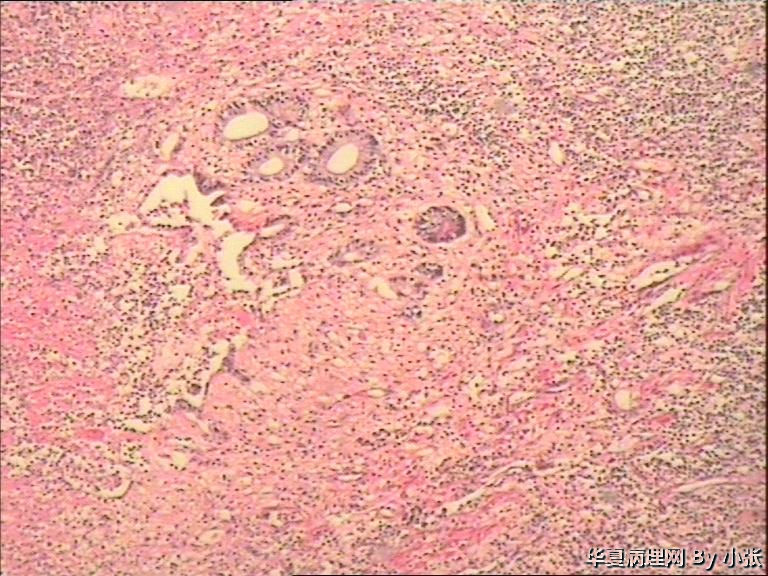

粘膜面布满大小不等的灰白色息肉样物,镜下粘膜面坏死,坏死下面是小淋巴细胞样细胞。系膜淋巴结的组织像好像也被破坏了。各位老师看看这个是什么东东?病人可能不出去会诊了,具体结果有待大家讨论。

小淋巴细胞性淋巴瘤?

MALT,MCL.肠病相关T

多发性淋巴瘤性息肉病

弥漫的小淋巴细胞增生,有淋巴上皮病变,这些小淋巴细胞上传的图像核不是很清楚,或者就是较深染的表现,细胞较小,之间有空隙,接近边缘带细胞的大小和形态特点,考虑为黏膜相关型结外边缘区B细胞淋巴瘤(MALT-MZL),实在没条件也应该建议染一下CD20和CD3。

需要和套细胞淋巴瘤鉴别。

镜下表现为粘膜面布满大小不等的灰白色息肉样物,本身就是多发性淋巴瘤性息肉病的特征。

再加上镜下细胞形态过于单一,不像MALToma中细胞还有分化